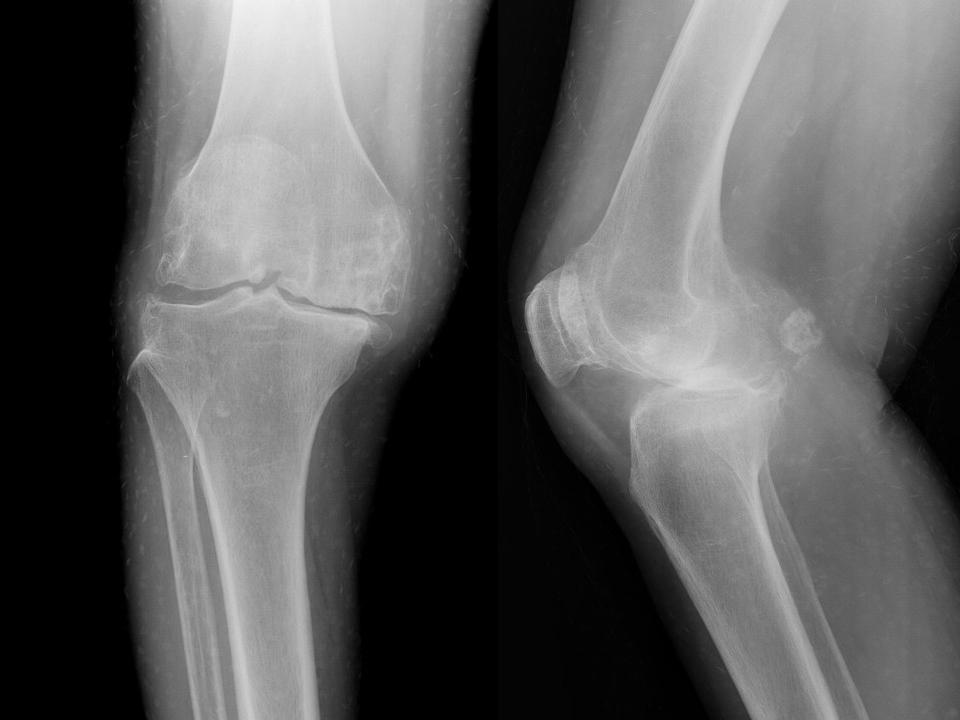

影像学检查 X线 四个方向X线影像 l 早期可无改变 l关节间隙变窄、不均匀、消失(成人<3mm; 老年人<2mm)。 l骨赘形成 l关节内游离体、骨质疏松 l软骨下骨板硬化、囊性变

膝关节骨性关节炎分期(阶段)